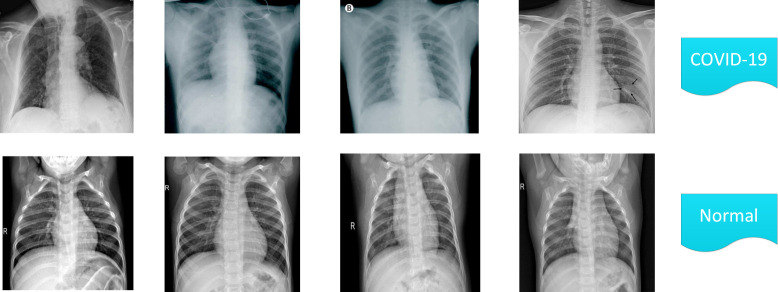

In this section, we introduce two well-known open-source image datasets named as Mendely and Kaggle which are the most commonly used datasets to analyze deep learning algorithms for COVID-19 diagnosis. In order to make a fair comparison between the proposed method and other benchmarks, we convert both datasets to 224*224 pixels which is a general rule for CNNs to get the same size. Furthermore, 80% of each dataset is considered for training purpose and the remaining images are utilized for testing. In Mendely dataset [65],1 there are 1800 images, with 1510 images in normal cases, while the rest of the cases are influenced by COVID-19. The Kaggel dataset2 also includes 1735 images, of which 825 images are related to cases with COVID-19 and the remaining 910 X-ray images are related to individuals who are not infected with COVID-19. To better understand the existing samples of individuals affected by COVID-19 and also to have normal conditions, we show some samples of X-ray images in both databases in Fig. 3, Fig. 4 by their conditions.

Fig. 3.

Four Samples of the X-ray-based Mendely dataset.

Fig. 4.

Four Samples of the X-ray-based Kaggle dataset.